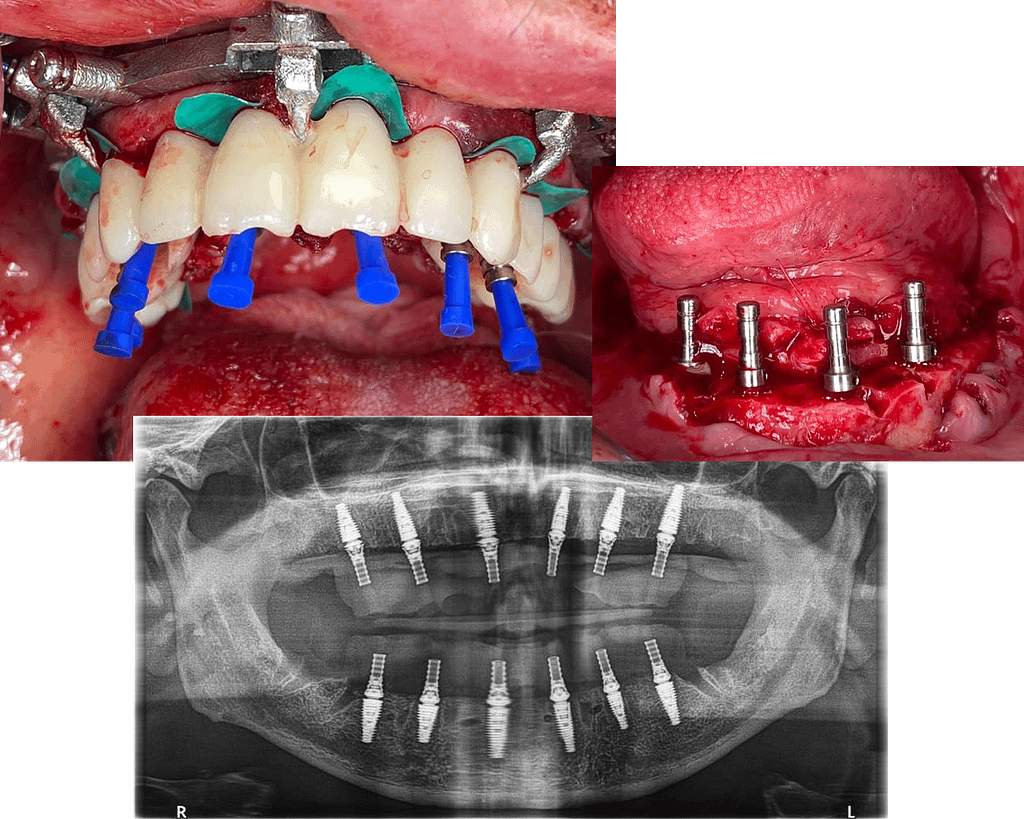

Before

After